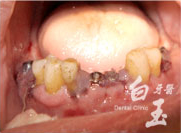

糖尿病嚴重牙周病-王先生

治療前

治療過程

治療中